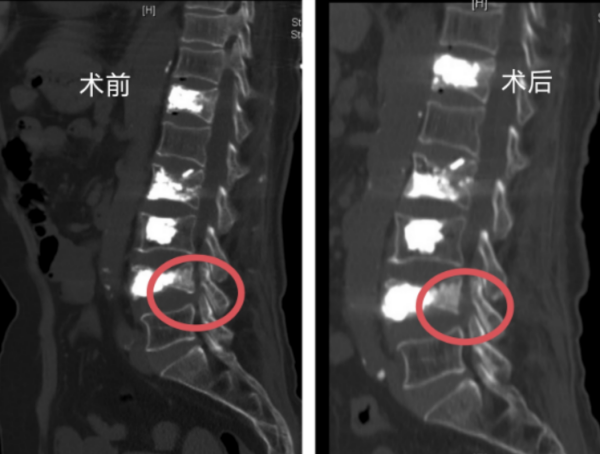

香港马会app 脊柱外科一区主任许宇霞接诊后,综合分析患者腰腿痛应该仍与骨折椎体有关。张纯华入院后接受CT及核磁共振检查,许宇霞发现其腰4椎体下缘近椎间孔处有一活动性骨块,当张纯华站立行走时,骨块因椎间盘形态改变移位,刺激出口神经根,导致她出现腰臀部及左下肢麻、胀、痛症状,且在活动后症状加剧。查明病因后,许宇霞主任团队很快为老人实施了椎间孔镜下腰椎减压术,取出了部分骨块,松解了受压的神经根,手术顺利完成。

核磁影像术前术后骨块对比

“脊柱骨折后一定要完善相关检查,很多患者认为做了X线检查后,再做核磁共振、CT检查是重复检查,费钱又费时间。需要明白的是,CT检查可以明确骨折的性质,是否为爆裂骨折,是否有椎体后缘骨块侵入椎管压迫神经,磁共振的优势是可以发现有无神经受压,受压是否严重,这个优势是无法替代的。”许宇霞强调,该患者就是在做了核磁共振及CT后,确诊有活动性骨块移位到椎间孔,压迫了坐骨神经。诊断明确后,即可在椎间孔镜下解决问题。